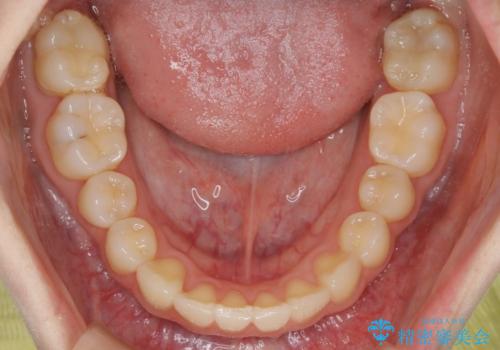

- 笑った時の歯の見え方を治したいとのことで矯正相談にいらっしゃいました。

一見そこまで大きなガタつきはないようにも見えますが、前歯の角度の不揃いや噛み合わせのズレなどから見え方に影響が出てしまっていました。

抜歯は全く必要のないレベルのガタつきだったため、マイクロインプラントを用いて歯全体を後方に移動させていくことできれいな歯並びを獲得することができました。

マウスピースとマイクロインプラントを組み合わせることで、抜歯をしなくても歯並びを治すためのスペースを作ることができます。奥歯から順に移動させていくので前歯に変化が出るまでには時間がかかりますが、どの分健康な歯を抜歯することなく理想的な歯並びを手に入れることができます。